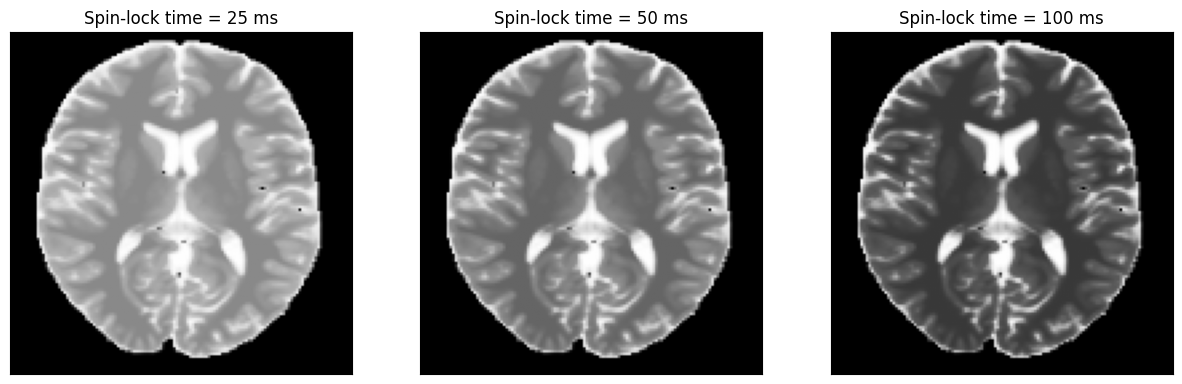

We can now plot the images at different inversion times.

spin_lock_times = sequence.get_definition('TSL')

idat = idata.data.abs().numpy().squeeze()

fig, ax = plt.subplots(1, idat.shape[0], figsize=(5 * idata.shape[0], 5))

for i in range(idat.shape[0]):

ax[i].imshow(idat[i, :, :], cmap='gray')

ax[i].set_title(f'Spin-lock time = {int(spin_lock_times[i] * 1000)} ms')

ax[i].set_xticks([])

ax[i].set_yticks([])

_images/587c434a1b4935607933e0d9c81a4a3e1d00e9e944137156f4207528f718843d.png